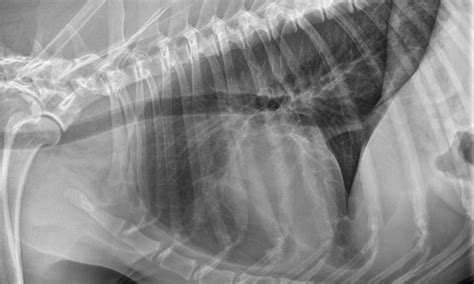

What Are The Symptoms Of Hemangiosarcoma In Dogs : Cutaneous Lymphoma In Dogs Pictures - Goldenacresdogs.com : Symptoms it may be difficult to notice the symptoms of hemangiosarcoma since in most cases it affects the internal organs.. My dog, who is 12 years old and is a corgi, had a surgery on june 24th to remove a uh, hemangiosarcoma tumor, that was quite large. Most dogs are not symptomatic until the advanced stages of the disease. Hsa is a malignant tumor of the blood vessels and can therefore develop anywhere in the body, commonly in the heart, spleen, liver and skin. Dogs with hemangiosarcoma occurring inside the body may have symptoms related to blood loss into the abdomen or the space around the heart, resulting in weakness, lethargy, or pale gums. On august 5, 2020, our dog sydney was diagnosed with hemangiosarcoma during a visit to the emergency vet for what i believed was bloat.

As such, it can spread to just about any organ that is connected to these vessels, but it most commonly metastases to the liver and lungs, as well as the heart. Hsa is a malignant tumor of the blood vessels and can therefore develop anywhere in the body, commonly in the heart, spleen, liver and skin. It is a cancer made up of the cells that line blood vessels, and therefore can be found in any part of the body. The dog may show weakness, especially in the hind legs, and decreased energy and reduced activity that lasts for a day or two, then goes away only to reappear weeks or months later. The cancer mimics a benign tumor, so you may notice some changes in your dog's behavior. Symptoms because hemangiosarcoma tumors grow internally, there is often very little warning until severe symptoms occur. Some of the most common symptoms include: The most common symptoms he sees are due to anemia from bleeding in the abdominal cavity … Read here about the symptoms, diagnosis and what. The tumors invade and erode blood vessels, which can cause a considerable amount of blood to seep into the abdominal or, less commonly, the thoracic (chest) cavity. Often, owners do not realize their dog is affected until the sudden hemorrhage or collapse. This is the scientific term for the cells that are the inner lining of veins, arteries, and capillaries. If the hemangiosarcoma occurs in the skin, muscles, or bone, a swelling may be visible beneath the skin.

Hemangiosarcoma in dogs is an aggressive, malignant tumor of blood vessel cells. Typically, hemangiosarcoma develops in the vascular endothelium. A rupture can occur without any warning and the symptoms may be noticed depending on the location of the tumor or the organ affected. Most dogs are not symptomatic until the advanced stages of the disease. Unfortunately, it's usually not until a tumor erupts and causes a severe internal bleed that the diagnosis is made. Dermal tumors manifest on the abdomen or in areas where the hair is thin. If the hemangiosarcoma occurs in the skin, muscles, or bone, a swelling may be visible beneath the skin. Hemangiosarcoma in dogs accounts for about 5 to 7% of all malignant cancers. Vague signs like the ones listed below could be caused by a variety of common illnesses in dogs. Symptoms of hemangiosarcoma may vary depending upon the region of tumor growth. Hemangiosarcoma of the spleen, or spleen cancer in dogs, is a cancer that is diagnosed in many canines every year. The cancer mimics a benign tumor, so you may notice some changes in your dog's behavior. Hsa is a malignant tumor of the blood vessels and can therefore develop anywhere in the body, commonly in the heart, spleen, liver and skin.